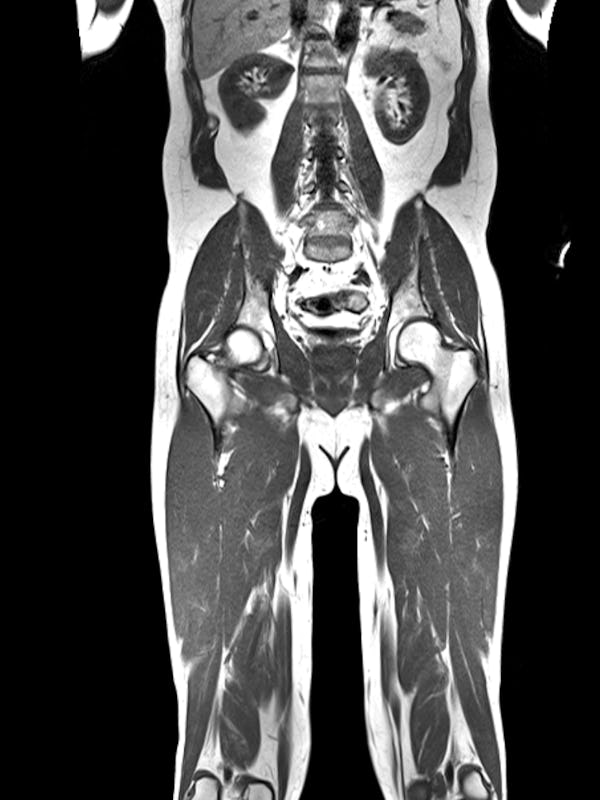

The best part were the images.

My whole body, bisected and laid bare for inspection.

Example scans, courtesy of Prenuvo.